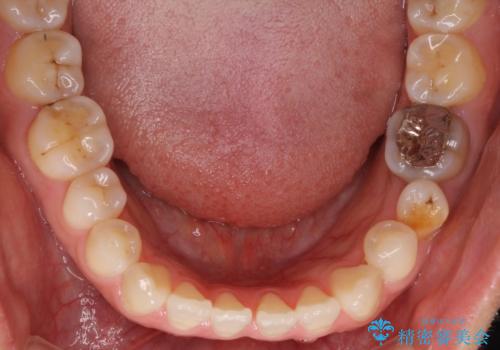

- 上下の前歯の隙間を気にして来院された患者様です。

インビザラインを用い、上下歯列のスペースを閉じていくこととしました。

治療期間中は奥歯がほとんど咬めない状態が続き、食事に大変苦労されました。

最終的には隙間もしっかりと閉じ、奥歯も咬みやすい状態でしあげることができました。